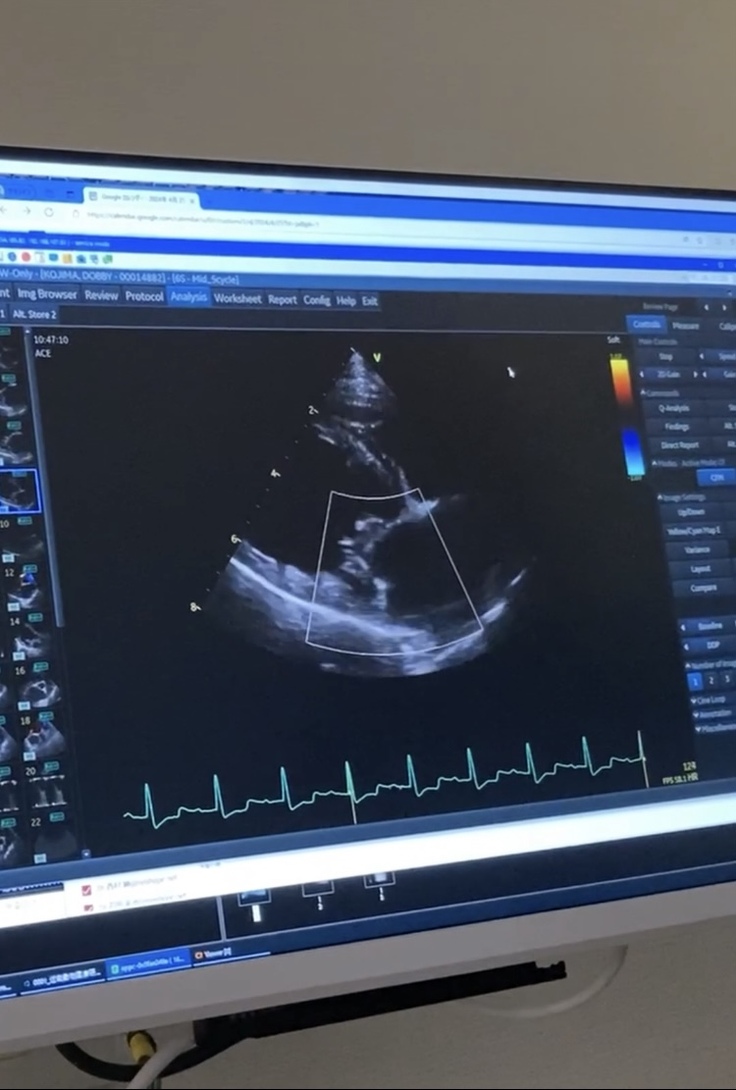

術後 弁が繋がれている様子